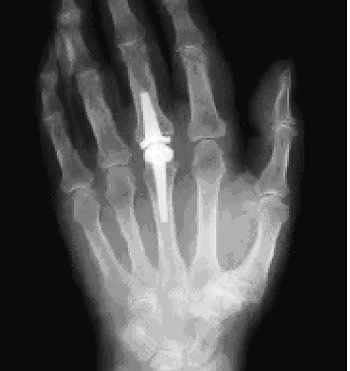

Röntgenaufnahme (Foto: Klinik Bleicherode)

Dass in Bleicherode große Gelenke wie Hüfte und Knie durch Prothesen ersetzt werden – und das in recht großer Anzahl – ist in der Region allgemein bekannt. Aber auch für andere Gelenke gibt es die Möglichkeit des Gelenkersatzes, wenn die nichtoperative Behandlung ausgereizt ist. So auch bei Herrn E., der sich mit Beschwerden in einem Fingergrundgelenk in der Rheumasprechstunde der Klinik vorstellte. Alle nichtoperativen Möglichkeiten waren bereits ausgeschöpft, sodass für ihn eine andere Behandlung gefunden werden musste: Im März 2011 ersetzten die Bleicheröder Ärzte daher das Fingergrundgelenk durch ein Kunstgelenk aus Pyrocarbon.

Natürlich ist es mit der Operation alleine nicht getan, erklärt Oberärztin Anke Druschke, Expertin für Rheumaorthopädie der Klinik. Um langfristig ein optimales Operationsergebnis und eine gute Funktion der Hand im Alltag zu erzielen, ist vielmehr eine individuelle Nachbehandlung gemeinsam mit Orthopädietechnikern und Ergotherapeuten erforderlich. Auch darum

kümmern wir uns in der Klinik in Bleicherode.